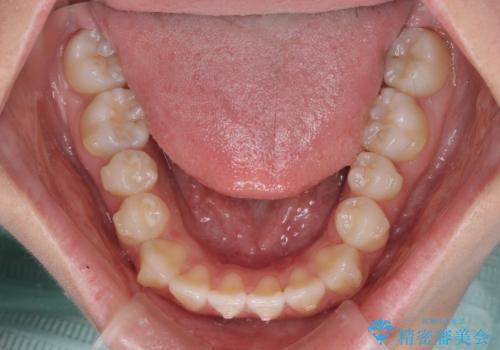

- 前歯のクロスバイトが気になり、インビザラインによる矯正治療を希望して来院された患者様です。

上顎側切歯(上の真ん中から2番目の歯)が舌側転位している場合、インビザラインでは仕上げきれないことが多く、更には無理して動かそうとすると歯髄壊死を起こすリスクが高いと言われています。

インビザラインで歯列を移動する前に、上顎前歯をワイヤー矯正で整え、その後上下歯列をインビザラインにて矯正治療を行うこととしました。

舌側転位している側切歯特有の、切縁の位置が不揃いであったり、根元が内側に引っ込んだ状態であったりという、インビザライン独特の仕上がりになることなく、きれいに整った歯列とすることができました。